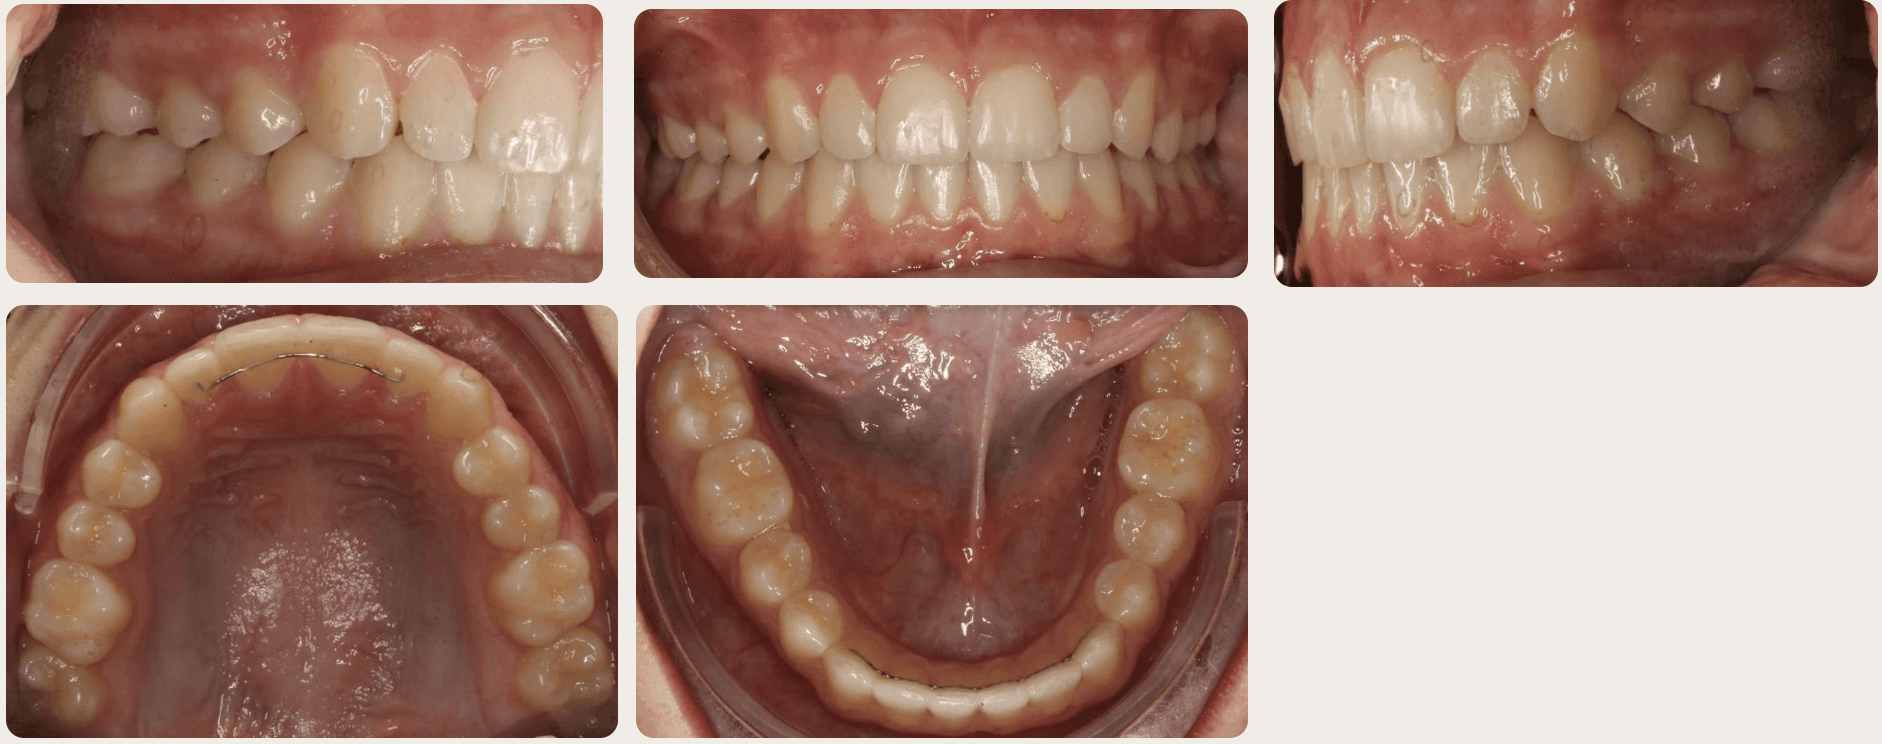

Final results

INTRAORAL